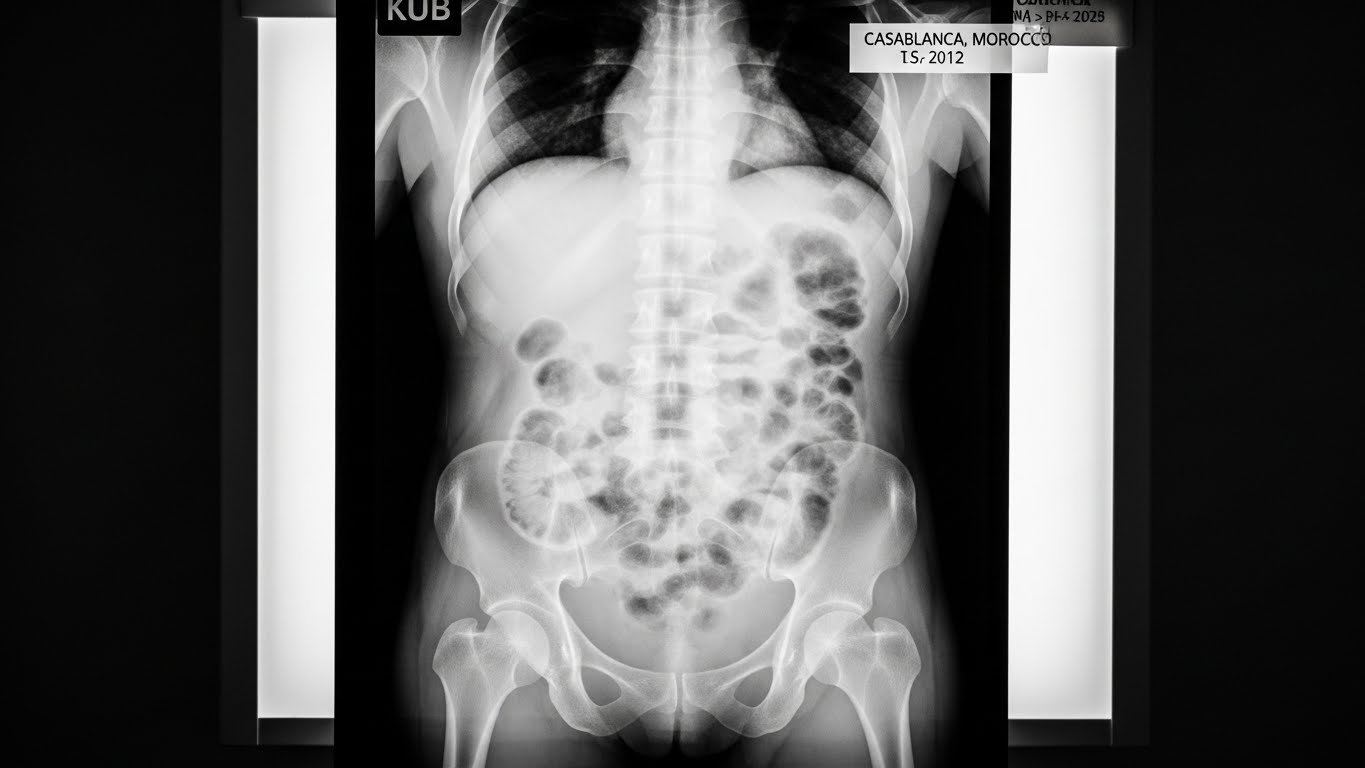

La radiographie de l’abdomen sans préparation, communément appelée ASP, est un examen d’imagerie médicale qui utilise les rayons X pour visualiser les organes de la cavité abdominale. Selon les recommandations de la Haute Autorité de Santé (HAS), cet examen reste un outil de première intention essentiel dans l’évaluation des urgences abdominales.

L’examen repose sur le principe de la radiographie conventionnelle : les rayons X traversent votre corps et sont captés par un détecteur numérique. Les différents tissus absorbent les rayons X de manière inégale, créant ainsi une image en nuances de gris :

- Les structures denses (os, calculs) apparaissent blanches

- Les organes mous apparaissent dans diverses nuances de gris

- L’air et les gaz apparaissent noirs

Cette technique permet de visualiser par transparence plusieurs structures abdominales : l’intestin, l’estomac, les reins, la vessie, ainsi que le squelette adjacent (vertèbres lombaires, bassin, dernières côtes).

Ce que l’ASP peut détecter

L’ASP révèle plusieurs anomalies caractéristiques que les radiologues recherchent systématiquement :

Anomalies liées aux gaz intestinaux :

Niveaux hydro-aériques (NHA) Ce sont des interfaces horizontales entre liquide (en bas) et gaz (en haut) dans les anses intestinales. Leur présence multiple et étagée signe une occlusion intestinale. Les radiologues distinguent :

- Les NHA grêles (nombreux, centraux, disposés en « échelle »)

- Les NHA coliques (moins nombreux, périphériques, plus larges)

Distribution anormale des gaz L’ASP montre normalement du gaz dans l’estomac et le côlon. Une absence totale de gaz colique avec distension grêle évoque une occlusion basse. À l’inverse, une distension gazeuse généralisée suggère un iléus paralytique.

Pneumopéritoine La présence d’air sous les coupoles diaphragmatiques (visible sur le cliché debout) traduit une perforation d’organe creux. C’est un signe d’urgence chirurgicale absolue nécessitant une intervention rapide.

Anomalies calciques :

Calculs rénaux et urétéraux Environ 80% des calculs urinaires sont radio-opaques. Ils apparaissent comme des opacités denses sur le trajet des voies urinaires. Les calculs uriques purs (20% des cas) ne sont pas visibles sur l’ASP.

Calculs biliaires Seulement 10 à 15% des calculs biliaires sont suffisamment calcifiés pour être visibles sur l’ASP. L’échographie reste l’examen de référence pour la vésicule biliaire.

Calcifications pathologiques L’ASP peut révéler des calcifications anormales : pancréatiques (pancréatite chronique), vasculaires (athérosclérose aortique), ou tumorales.

Autres anomalies :

- Fécalomes : Masses de matières fécales impactées dans le côlon

- Corps étrangers métalliques : Bien visibles s’ils sont radio-opaques

- Anomalies osseuses : Tassements vertébraux, lésions du bassin visibles accessoirement